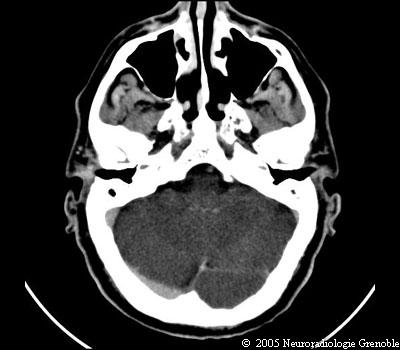

Radioanatomie TDM de l'encéphale

TDM cérébrale sans injection